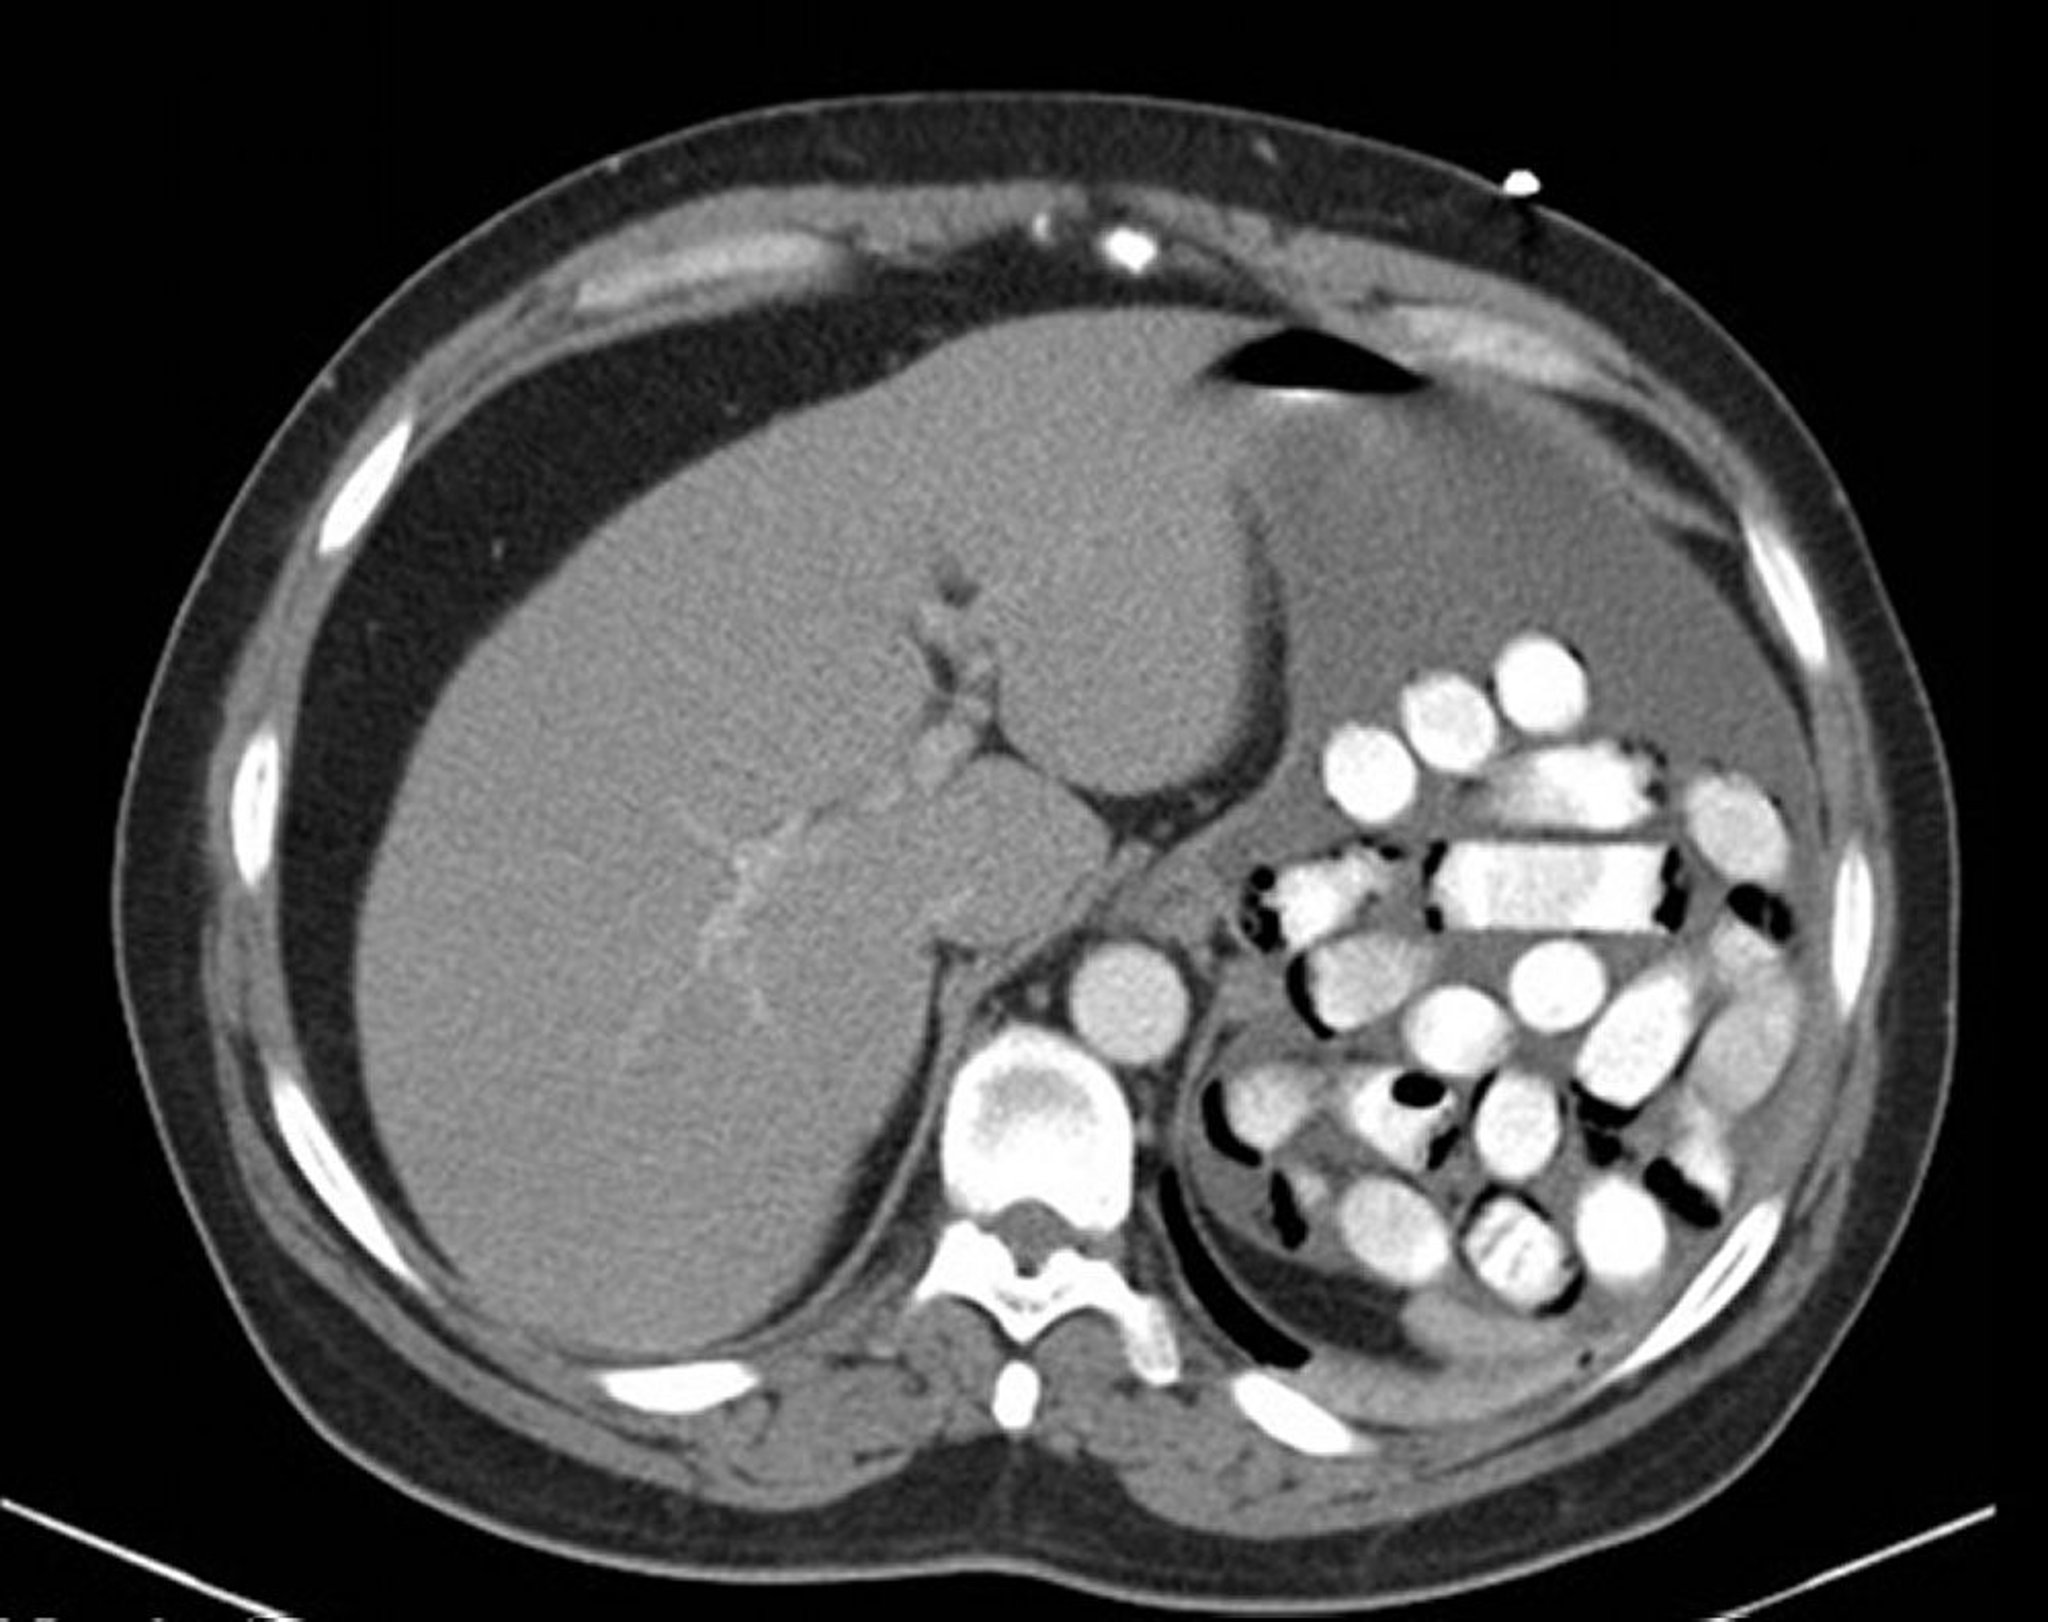

Cuerpo extraño en el estómago (TC)

Esta imagen muestra los paquetes de droga en el estómago.

Imagen proporcionada por Alan Gingold, DO.